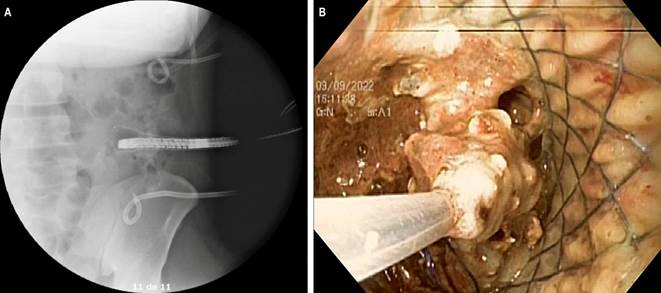

The procedure began with the medial pig-tail drain. Contrast medium was advanced, and under fluoroscopy, the drain was confirmed to be in the correct position. A Jagwire metal guidewire was then advanced through the drain, and the catheter was removed. The entry orifice was enlarged with a small 5 mm incision, and a 9 mm Savary bougie was advanced over the guidewire. A fully covered 16 cm esophageal stent was then advanced over the guidewire and deployed (Figure 2). A 12-15 mm dilation balloon was used to dilate the stent to 15 mm. An endoscope was then advanced through the stent, revealing a large cavity with necrosis and several drains inside. Using a loop, an endoscopic necrosectomy was performed to remove the abundant necrotic tissue, and the cavity was washed with saline solution. The stent was connected to a collection bag, and the drains were left in place for tidal irrigation (Figure 3).